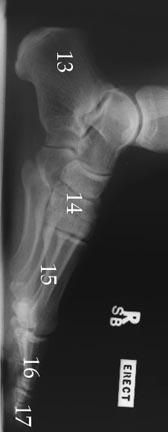

X-Rays

13. Calcaneus

14. Tarsals

15. Metatarsal

16. Proximal Phalanges

17. Distal Phalanges